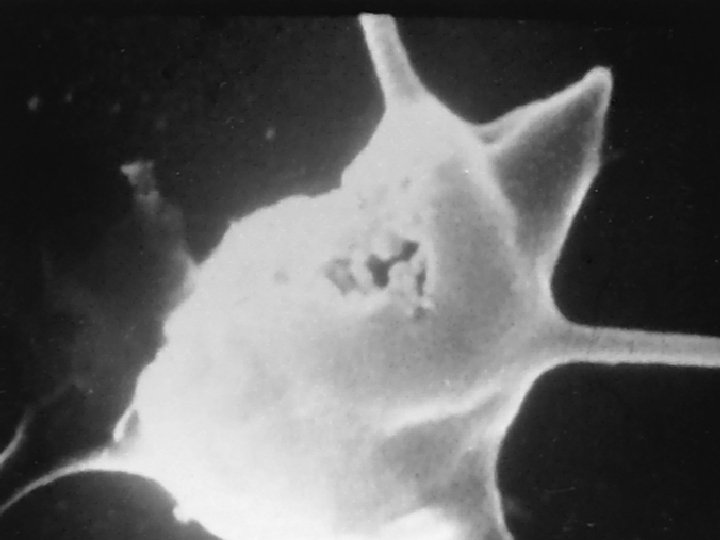

Composition of Blood Cellular components Leukocytes (white blood cells) ▪ Defend the body against infection and remove debris ▪ Granulocytes ▪ Membrane-bound granules in their cytoplasm ▪ The granules contain enzymes capable of destroying microorganisms ▪ Inflammatory and immune functions ▪ Capable of ameboid movement (diapedesis)

Composition of Blood Agranulocytes Monocytes and macrophages make up the mononuclear phagocyte system (MPS) Monocytes Macrophages Lymphocytes-T & B Natural killer (NK) cells